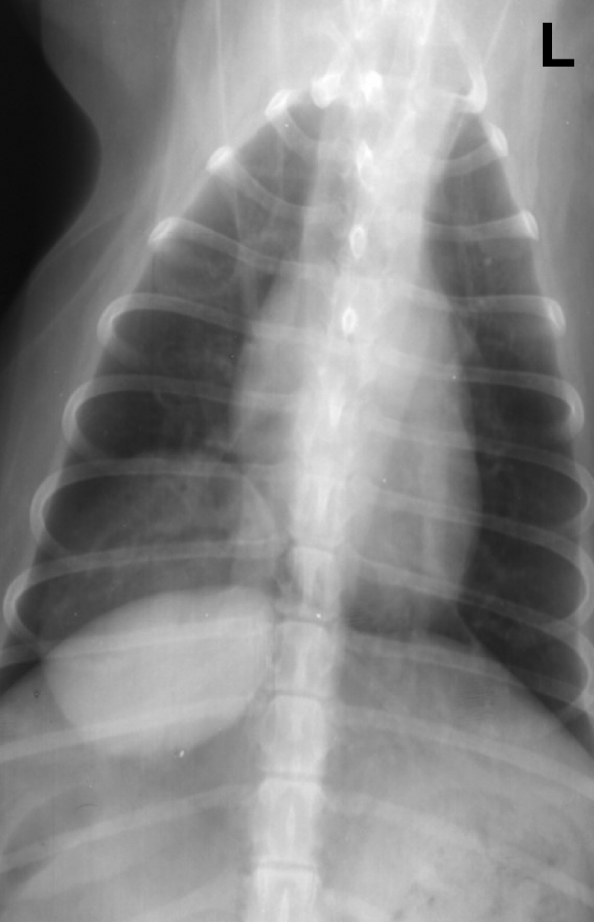

what kind of pattern

normal- left

interstitial- right